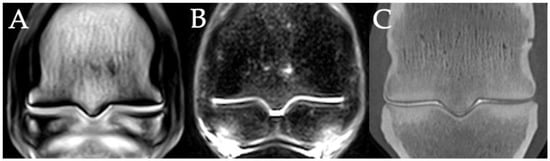

3.2. Sclerosis of the Subchondral and Adjacent Medullary Bone of the PSGs

4.2. Imaging Techniques